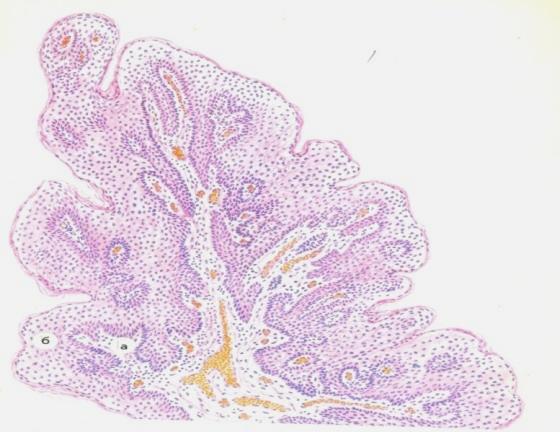

Карнификация Легкого: Микропрепараты и Диагностика

Раздел: Калейдоскоп образов